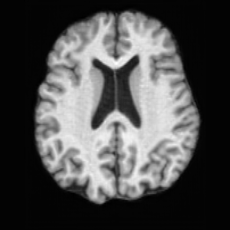

(a)PathologicalInput ImageSynthSR [18]Brain-ID [28]UNA [30]USBHealthyGround TruthRefer to captionRefer to captionRefer to captionRefer to captionRefer to captionRefer to captionRefer to captionRefer to captionRefer to captionRefer to captionRefer to captionRefer to captionRefer to captionRefer to captionRefer to captionRefer to captionRefer to captionRefer to captionRefer to captionRefer to captionRefer to captionRefer to captionRefer to captionRefer to caption(b)HealthyInput ImageConditionalLesion MaskUNA [30]USBRefer to captionRefer to captionRefer to captionRefer to captionRefer to captionRefer to captionRefer to captionRefer to captionRefer to captionRefer to captionRefer to captionRefer to captionRefer to captionRefer to captionRefer to captionRefer to caption

Figure 5: Comparison of bidirectional brain editing. (a) pathology-to-healthy, the circles and arrows highlight lesion regions and unsuccessful reconstructions; (b) healthy-to-pathology. Note that SynthSR and Brain-ID cannot perform healthy-to-pathology editing.

Pathology-to-Healthy Editing. Fig. 5 (a) presents comparison results on four input brain images with lesions of varying sizes, shapes, and densities. All competing models, although specialized for healthy brain image synthesis, struggle to reconstruct pathological regions, especially near lesion boundaries. In contrast, USB accurately reconstructs the corresponding healthy brain, even in challenging cases with large, high-density lesions where normal brain structures are almost completely obscured (last row). Tab. 2 provides a quantitative comparison for pathology-to-healthy editing, where USB achieves the best performance across all three datasets, demonstrating the effectiveness of its unified framework in reconstructing healthy brains from pathological inputs. Additional results are in Suppl. B.